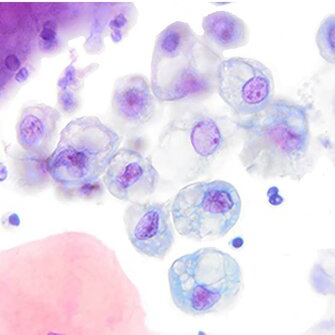

Cytology description

- Cohesive groups and dispersed urothelial cells with cellular and nuclear enlargement and maintained N:C ratio (Arch Pathol Lab Med 2023;147:1148)

- Variable combinations of the following features: dense to vacuolated cytoplasm, nucleomegaly with increased N:C ratio (> 0.5), nuclear vacuolization, vesicular to finely granular chromatin, prominent nucleoli, nuclear hyperchromasia, smudgy / glassy nuclei, smooth to irregular membrane, nuclear grooves

Cytology images